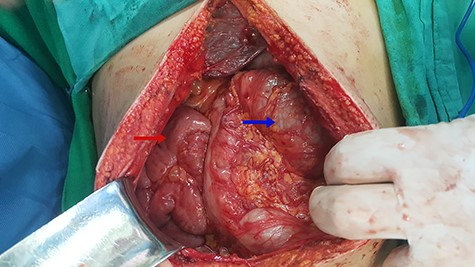

Laparoscopic surgery was excluded for technical and anatomical difficulties; we switched to open surgery. During intraoperative, we found malrotation (90° counterclockwise), where the small intestine was on the right side and the colons were on the left side (Fig. 2), and small intestine was slightly dilated and entrapped within a congenital hernia in the mesentery of the transverse colon (Fig. 3).

Red arrow indicates to the small intestine and blue arrow indicates to the colons.